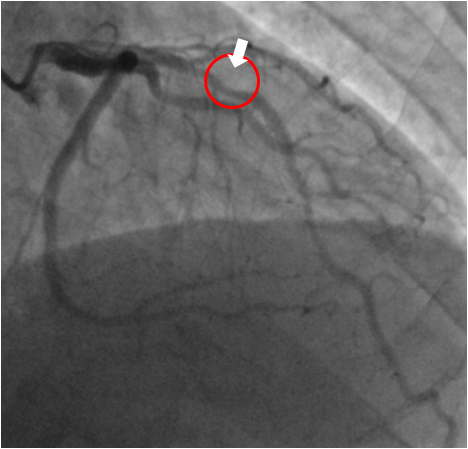

冠動脈疾患の可能性が高いと判定された場合は心臓カテーテル検査にて確定診断を行います。カテーテルと呼ばれる直径2mm程度の細い管を足の付け根や手首の動脈から挿入し、心臓の出口付近の冠動脈に引っ掛けて造影剤を注入、撮影を行い冠動脈の狭窄や閉塞の度合いを調べます。当院では殆どの症例において負担の少ない手首の血管から検査と治療を第一選択部位として行っており、治療を行った場合でも合併症がなくスムーズに終了した場合は通常1泊もしくは2泊で退院可能となります。

心臓カテーテル検査(冠動脈造影)にて狭窄や閉塞を確認した血管に対しては、バルーンやステントを用いて血管を広げて血流を確保します。

心臓カテーテル 治療前 心臓カテーテル 治療後